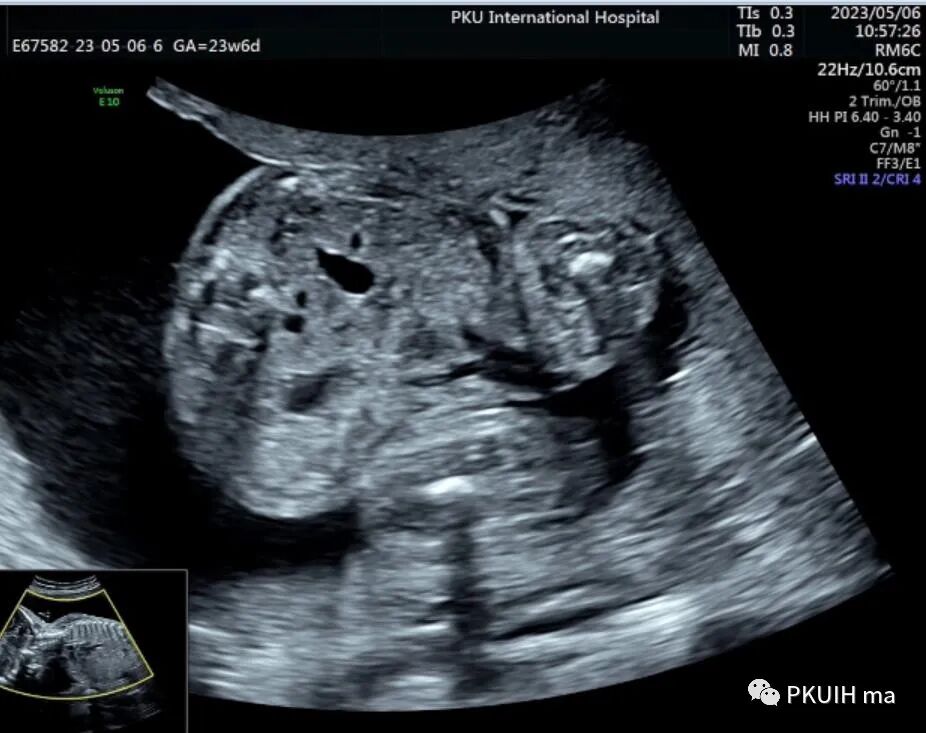

下图分别是23周和27周正常胎儿的肾横断面图像,显示肾门呈水平状,指向内侧,分离的肾盂也呈水平状